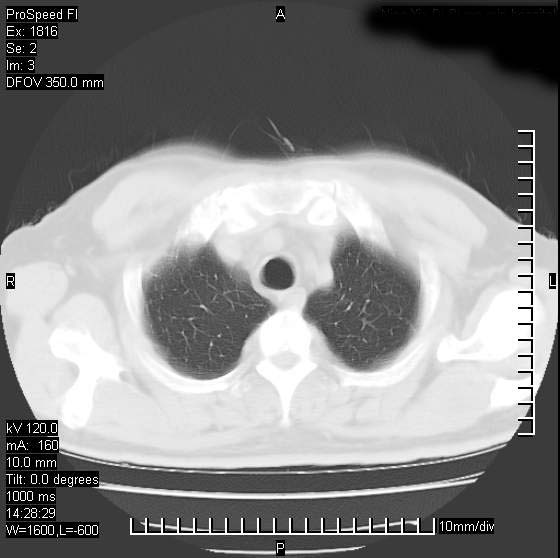

男性,50 ,肺结核9年,咳嗽,胸痛一周。右上肺见一厚壁空洞,周边有点样钙化,胸膜牵拉,洞壁较光整。诊断结核性空洞。有癌性的可能吗? 余肺野无异常,没有上传。

不像是肺ca倒更像一个结核空洞,因为看一下他内前方的支气管一点没有浸润征象只是压迫.

部分层面见空洞为近似新月形,洞壁内缘尚规整且近肺门侧,周围见索条影、卫星灶,结合病史,首先考虑肺tb可能大。